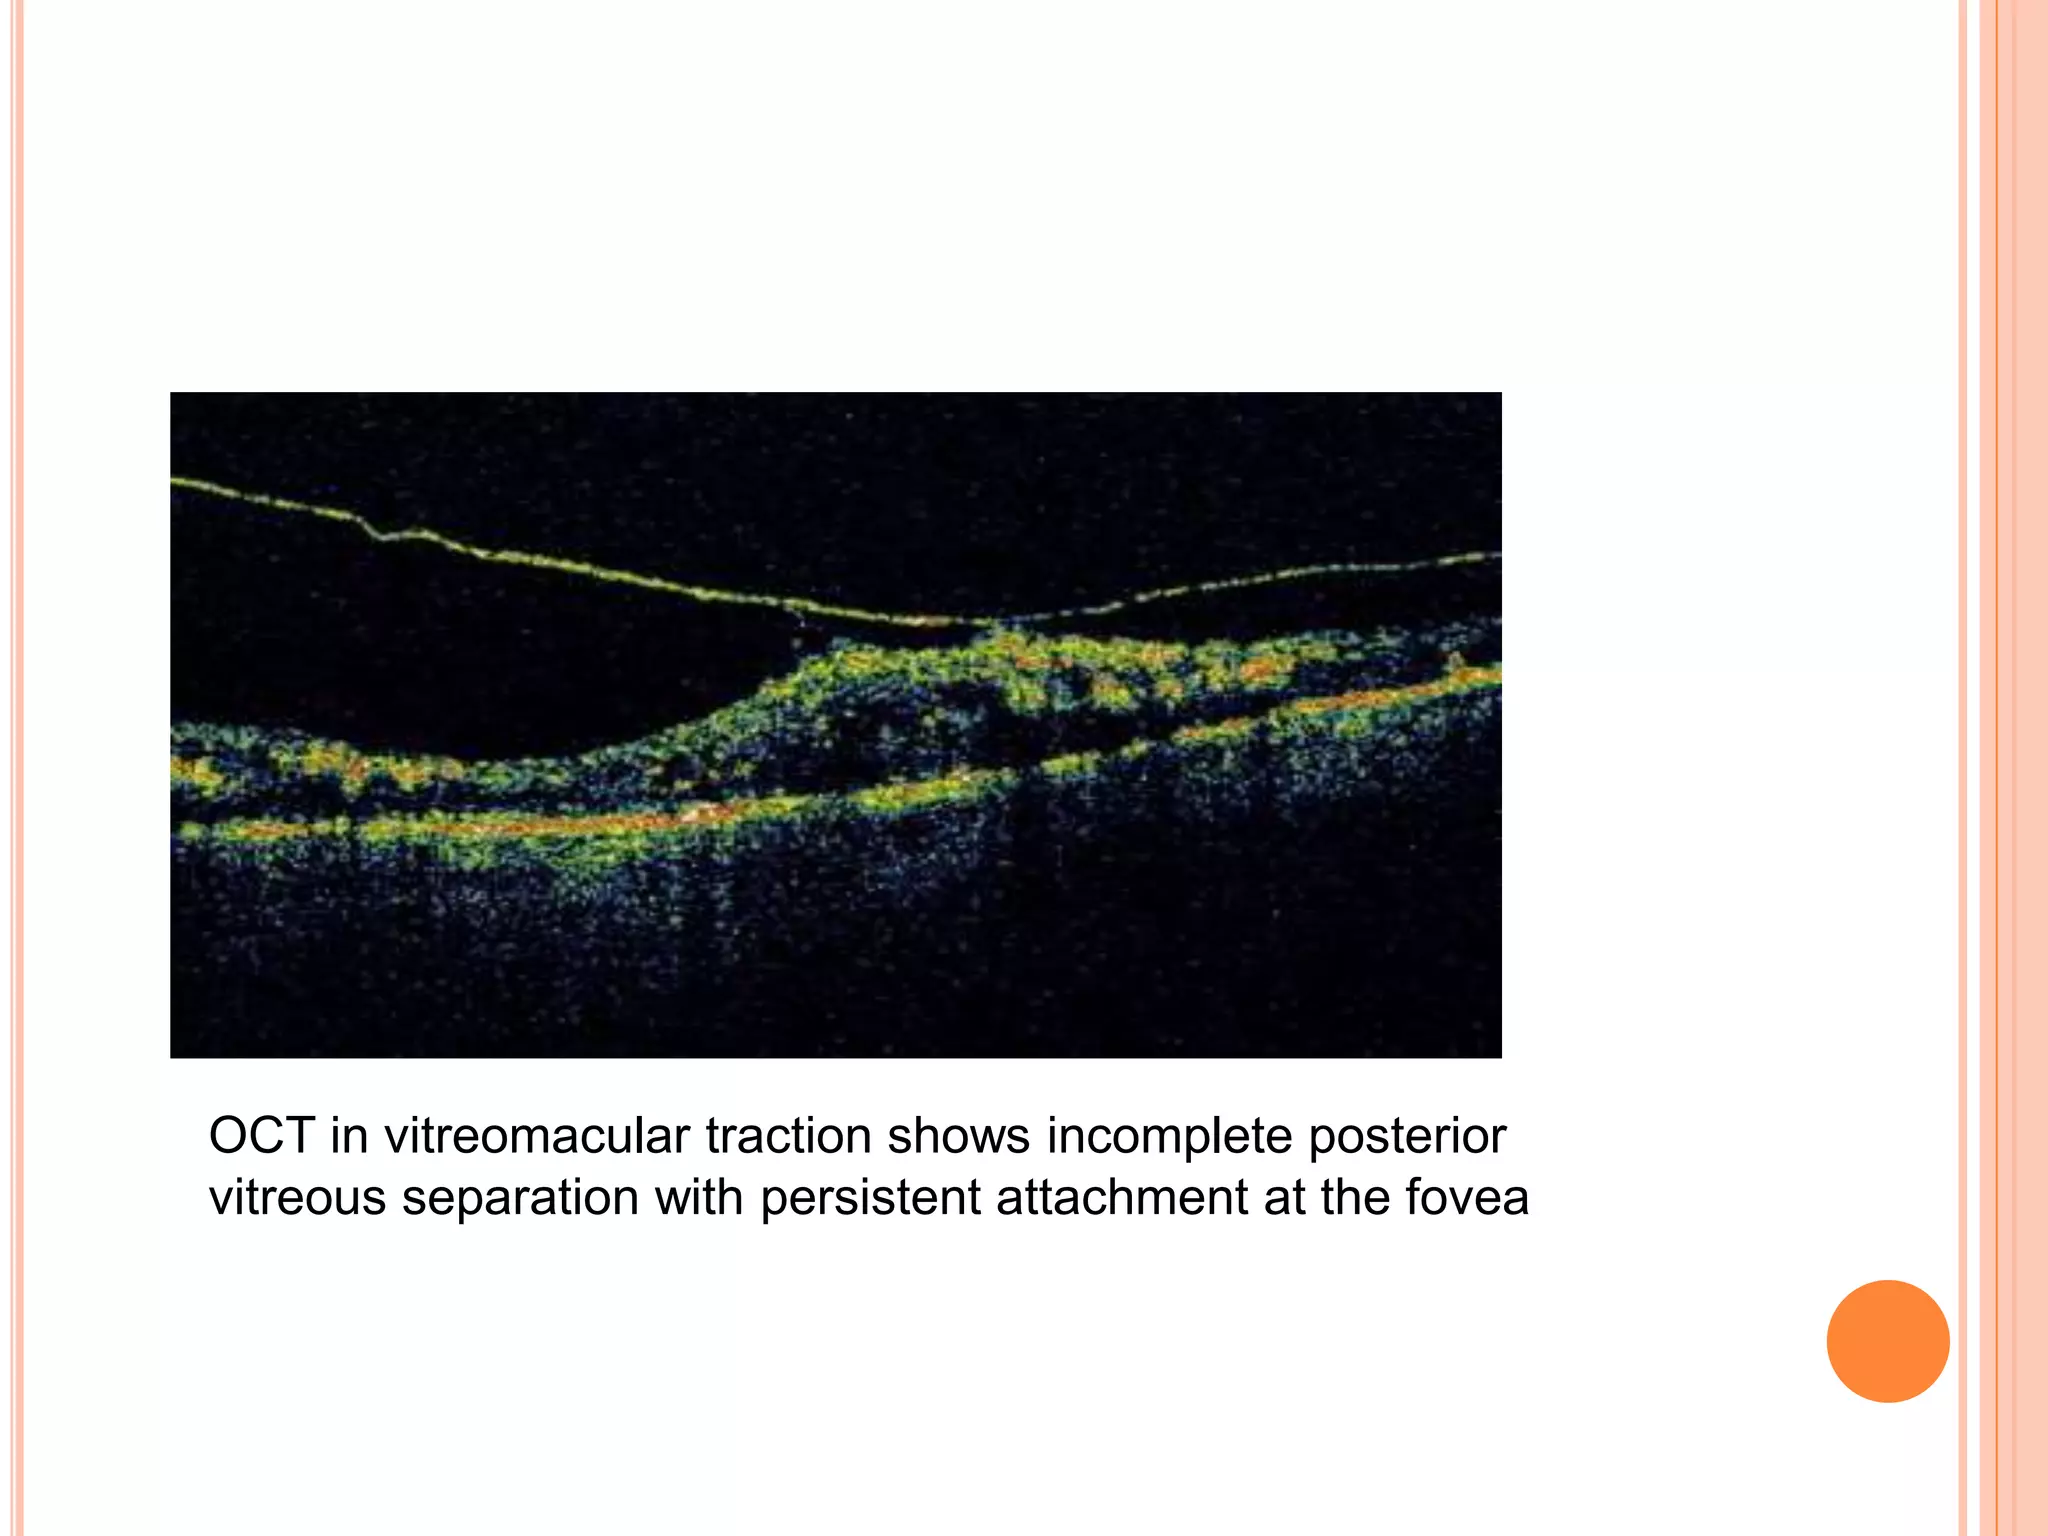

VIREOMACULAR TRACTION

 The vitreomacular traction is a complication of

anamolous partial PVD where the vitreous is

 OCT has probably become the principal ancillary

test for confirming the diagnosis of pathognomonic

vitreoretinal attachment .

OCT in vitreomacular traction shows incomplete posterior

vitreous separation with persistent attachment at the fovea